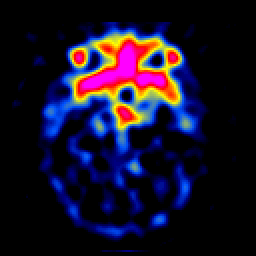

SPECT TL Study #4 -- Slice #17